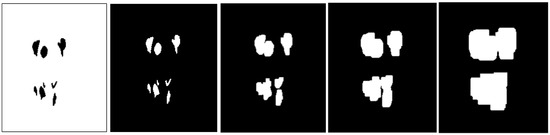

Appendix B.1. Multi-Level Distance Features